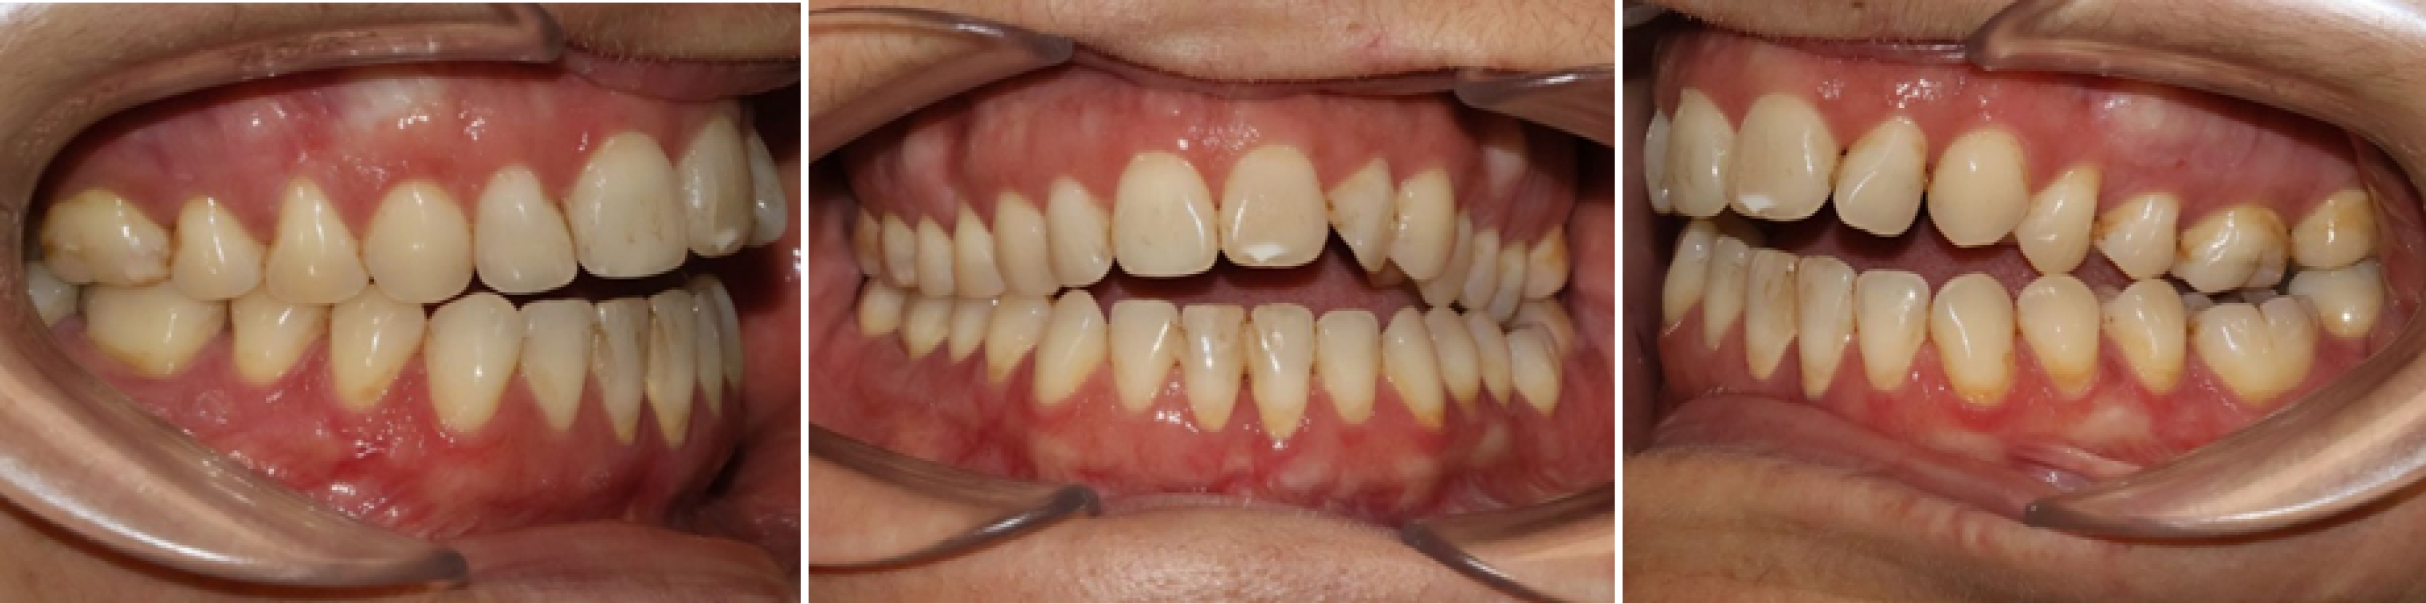

- • Des photographies